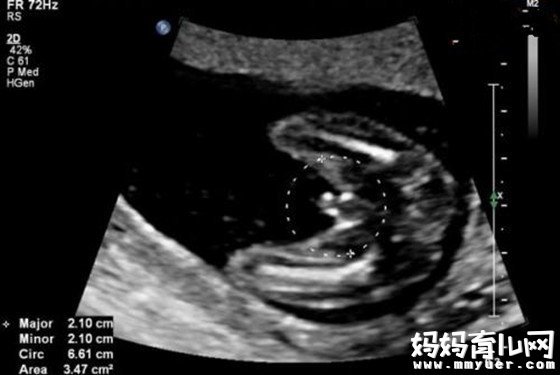

20周时的胎儿生长趋于平稳,此时您需要将更多的精力放到增强营养上。健康地进入孕中期你一定很欣慰吧,现在胎儿的身长已经达到16.5厘米,体重达到250克。

胎儿的感觉器官进入成长的关键时期,大脑开始划分专门的区域进行嗅觉、味觉、听觉、视觉以及触觉的发育。从孕20周起,胎儿的视网膜就形成了,开始对光线有感应,这时你可以用手电照射腹部进行胎教,他(她)对强光的反应会很大。